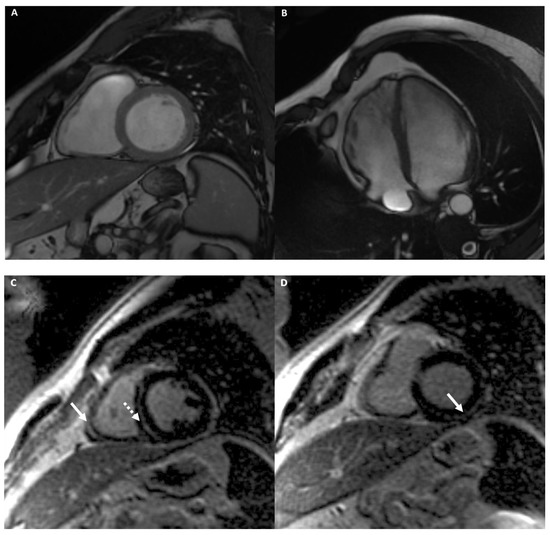

4.2.1. Cardiac Imaging: AH vs. Hypertrophic Cardiomyopathy

4.2.2. Cardiac Imaging: AH vs. Dilated Cardiomyopathy

4.2.3. Cardiac Imaging: AH vs. Left Ventricular Non-Compaction

4.2.4. Cardiac Imaging: AH vs. Arrhythmogenic Cardiomyopathy

Arrhythmogenic Right Ventricular Cardiomyopathy

Left Dominant Arrhythmogenic Cardiomyopathy (LDAC)

4.2.5. Cardiac Imaging: AH vs. Infiltrative Cardiomyopathy